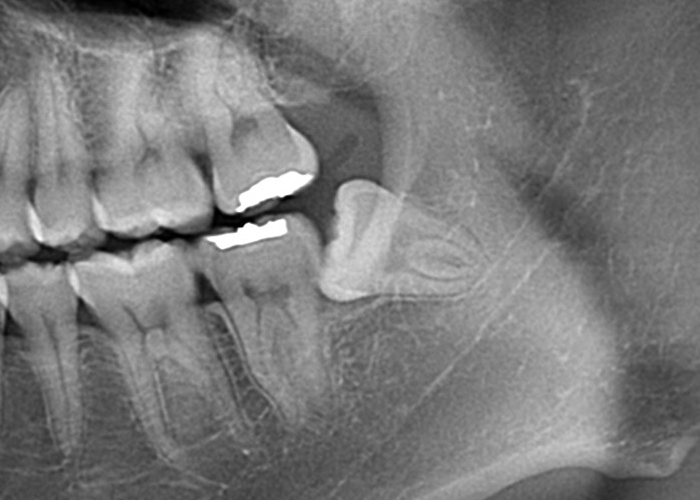

骨性完全埋伏智歯(骨に完全に埋まっている)

この場合も親知らずは通常、レントゲンやCTスキャンなどの画像検査でのみ確認できます。

完全埋伏の親知らずは、周囲の組織に直接的な問題を引き起こさない場合もありますが、将来的に問題を引き起こす可能性があります。

そのため、定期的な口腔検診や画像検査が重要です。

もしこのような歯が抜歯が必要となった場合は近隣口腔外科への紹介をする場合があります。